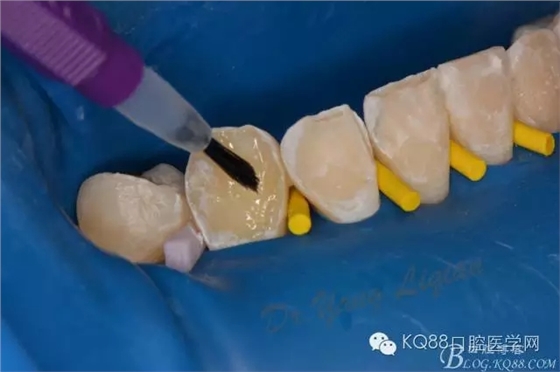

小美女今年16歲,正畸結(jié)束后下前牙唇側(cè)齲壞嚴重,影響美觀??紤]到患者年齡較小,所以和家長商量后決定現(xiàn)行樹脂貼面暫時修復,待成年后重新制定修復計劃。

圖片由助理拍攝,比較雜。31只是做了拋光沒有做貼面。齲壞脫礦位置質(zhì)地較軟,小球鉆仔細去除,硅膠車針拋光。